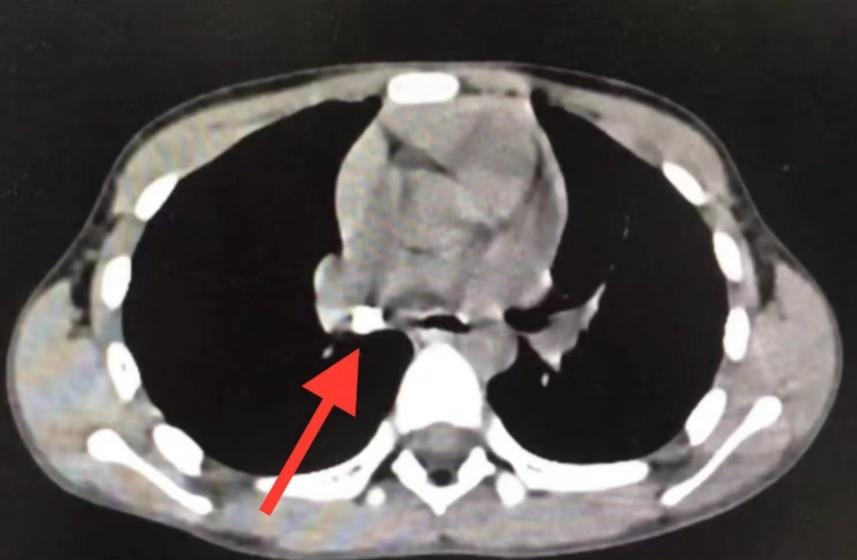

根据阳阳妈妈的线索,医生们决定立刻进行腹部X光平片检查,以进一步确定牙齿的位置。X光平片是一种常用的医学影像技术,能够显示身体内部的骨骼和组织结构,为医生提供诊断和治疗的依据。

图2 腹部平片显示右下腹见一牙齿样异物

经过X线检查,医生终于在阳阳的肠道影像上发现了那颗消失的牙齿,鉴于牙齿已经顺利进入肠道,且其体积较小,医生决定不进行胃肠镜检查,而是选择观察等待。第二天,阳阳在没有任何不适的情况下,成功地将这颗牙齿通过消化道自然排出。